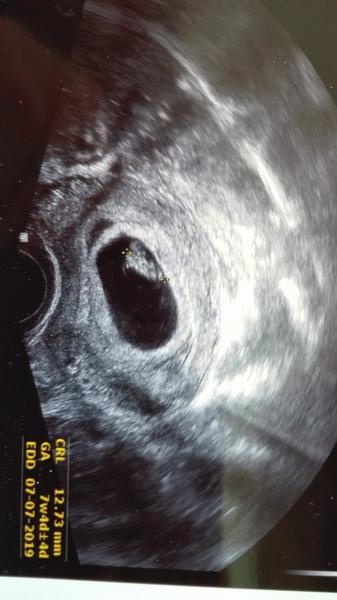

Ahoj holky, hlásím, že máme srdíčko, odpovidame opožděné ovulaci o asi 4 dny, což vím, že ji mám později než v půlce cyklu, takže vše zatím v pořádku😍, příště jdu do poradny až za tři týdny 11.12., nevím, jak to vydržím 🙈😅 a budou brát krev na 1.screening, snad se bude mimčo vyvíjet správně a tentokrát to nevzdá 😊 a na fotce vám představuji naší miminkovskou čmouhu 😎 já bych fotku ještě nebrala, ale manžel chtěl mimčo vidět 😀 mám velkou radost.